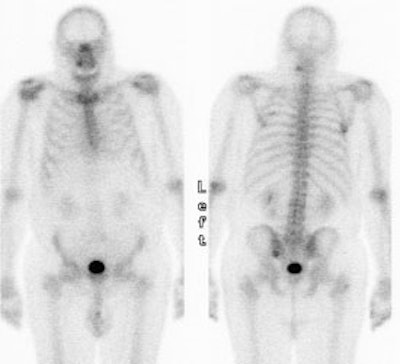

Unsuspected bone metastases: The patient shown below had a left lung non-small cell lung cancer (vaguely seen in the left lung on the PET images shown below). There was no uptake of tracer within the hila or mediastinum to suggest nodal metastases, however, unsuspected bone metastases were found in the right humerus and right hip (black arrows). These findings significantly altered patient management. |

|

Unsuspected bone metastases: The patient shown below had a cavitary left lung non-small cell lung cancer. There was no uptake of tracer within the aortopulmonary window lymph nodes detected on CT to suggest metastases, however, unsuspected bone metastases were found in the left anterior 4th rib (black arrow) and lumbar spine (red arrows- not included in staging lung CT scan). The presence of bone metastases significantly alters patient prognosis and management. PET imaging provides a rapid whole body survey for the detection of unsuspected metastatic disease. |